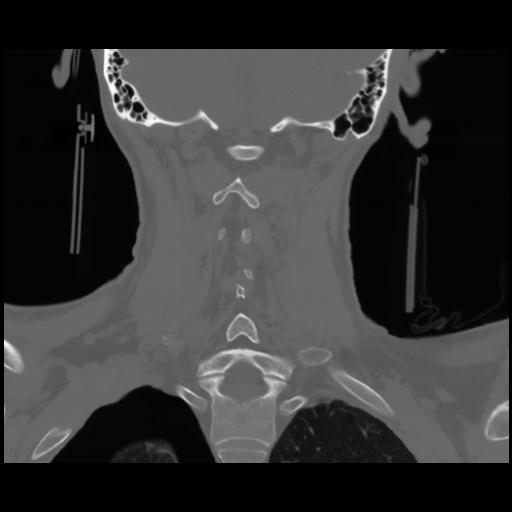

13 P.BLANDAS,,Coronal,2.000,P.BLANDAS,Coronal,